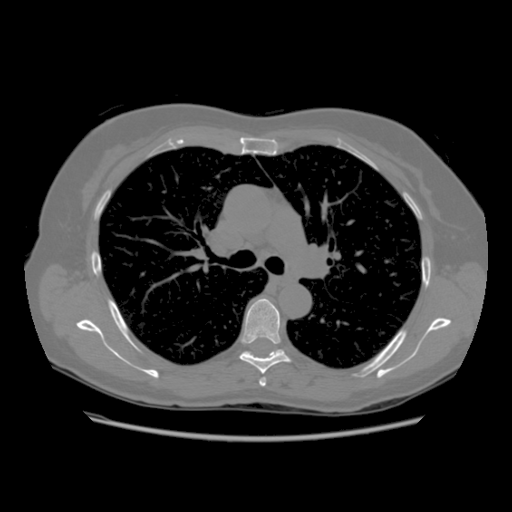

IV-C Few-View CT Reconstruction

In this section, the reconstruction performance of our proposed framework under few-view conditions will be tested. For the parallel and fan beam geometry, the number of views increases from to , uniformly distributing from to and to respectively. Such settings provide a complete benchmark of reconstruction performance, ranging from extremely sparse to relatively complete, full-view CT reconstruction. The experiment results are shown in Fig.5. Additionally, the ground truth, few-view ( views), and full-view ( views) CT reconstruction results of different methods are shown in the first and third rows of Fig.7 (parallel-beam, LIDC-IDRI dataset), and Fig.8 (fan-beam, LIDC-IDRI dataset).

To test the proposed framework’s performance on limited-angle reconstruction, we redo the experiment in the above section with the angular range changing from to for parallel-beam geometry and to for fan-beam geometry, one projection per degree. The experiment results are shown in Fig.6. Also, the ground truth and the limited-angle CT reconstruction results of different methods are shown in the row of Fig.7 (parallel-beam, LIDC-IDRI dataset), and Fig.8 (fan-beam, LIDC-IDRI dataset).

(a) Ground Truth

43.87dB/0.96

(b) ASD-POCS

47.96dB/0.97

(c) RBP-DIP

34.46dB/0.84

(d) DIP

26.63dB/0.93

(e) MED50

29.03dB/0.95

(f) RED-CNN